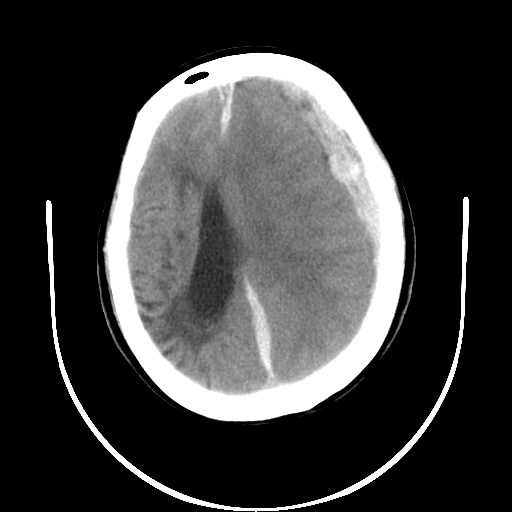

以下是引用gaoshengjiang在2007-10-7 9:18:00的发言:[br]左枕叶脑出血,左额颞顶部及纵裂硬膜下血肿,蛛网膜下腔出血,右颞叶脑梗塞。出血原因:患者年龄较大可能为动脉硬化或血管畸形?建议进一步临床检查。